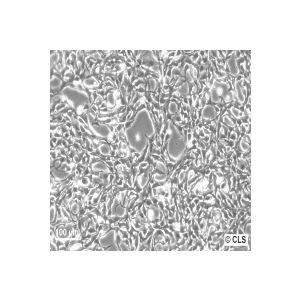

Breast cancer cell lines